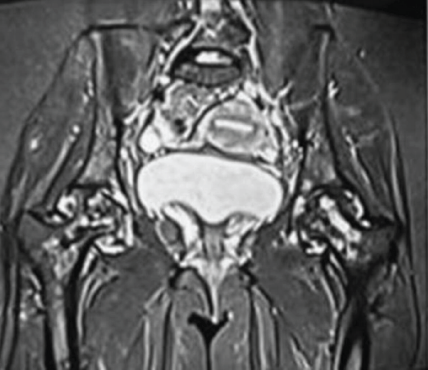

With these findings, a diagnosis of MSON was made. Investigations were conducted to exclude underlying conditions commonly associated with MSON, which included an evaluation for connective tissue diseases: Complete blood count, erythrocyte sedimentation rate, C-reactive protein, renal function test, rheumatoid arthritis factor, anti-nuclear antibodies, anti-ds DNA, lupus anticoagulant, and anticardiolipin antibodies; an assessment of coagulation profile: Prothrombin time, activated partial thromboplastin time, international normalized ratio, fibrinogen, antithrombin, protein C, protein S, factor V Leiden, and factor VIII; and testing for viral markers (HIV, Hepatitis B virus, Hepatitis C virus), all of which returned negative results, thereby ruling out any underlying diseases. The patient’s history ruled out drug usage, alcohol usage, and exposure to hyperbaric environments (eliminating Caisson’s disease). She underwent core decompression and bone marrow aspiration concentrate (CD and BMAC) application sequentially in all affected joints in 3 sessions with a 2-month gap. Shoulders were first addressed, and knees and ankles were addressed last, and advised Alendronate 70 mg once a week after shoulder surgery for 3 years. When evaluated after 18 months of surgery, the pain Visual Analog Scale (VAS) in the shoulder decreased from 9/10 to 0/10 (Fig. 1c). In the hips, VAS of 6/10 decreased to 0/10 after 1 month of surgery. But after 9 months, it gradually increased to 9/10. Radiological assessments indicated that both hips advanced to Stage III, with the right hip showing a greater deterioration than the left (Fig. 5). Thus, she underwent TFL muscle pedicle bone grafting to both hips after 2 years of primary surgery, following which VAS scores gradually decreased to 2/10 on the right side and 0/10 on the left side (Fig. 6). VAS decreased from 9/10 to 4/10 in the right ankle and from 9/10 to 4/10 in the right knee. The left ankle and knee remained pain-free in both pre-operative and post-operative periods. The patient is walking independently now.

Figure 5: Magnetic resonance imaging of both hips post-core decompression. 1.5 T. Short tau inversion recovery, coronal, showing heterogeneous hyperintense signals in both femoral heads with loss of contour of femoral heads (right > left) and joint space maintained, suggestive of Ficat-Arlet III stage of avascular necrosis. Stigmata of core decompression were seen at both femoral heads.